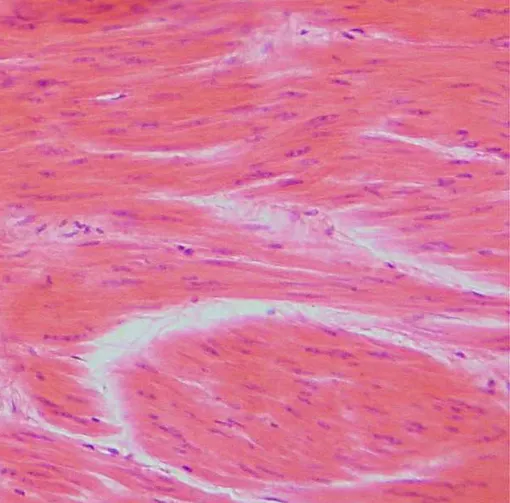

По своему гистологическому строение она имеет некоторые сходства со скелетной мускулатурой: тоже имеет поперечную исчерченность, поэтому специалисты иногда называют ее частным случаем поперечно-полосатой мышечной ткани.